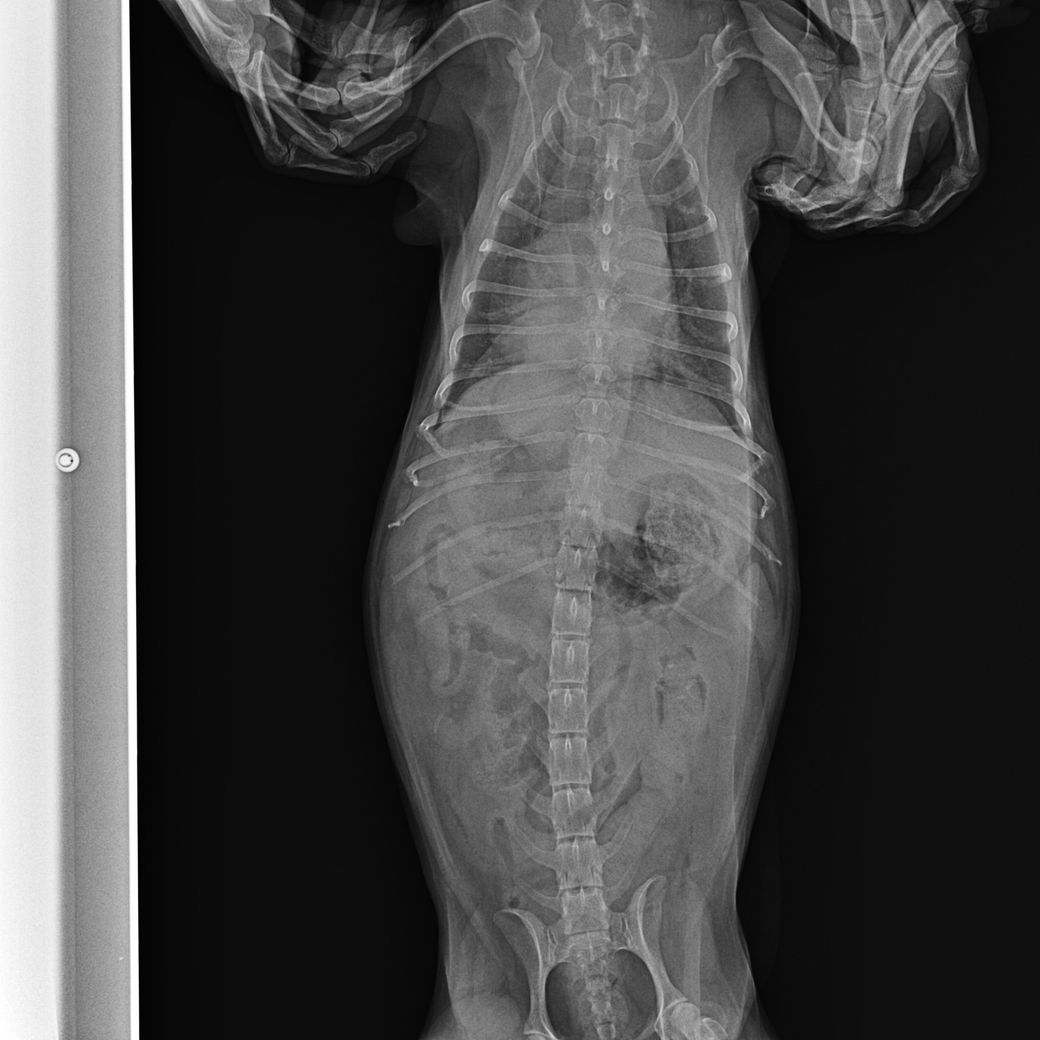

강아지가 식욕 저하와 기침을 많이 하고 거품 토를 해서 진료를 봤습니다. 헥헥거리는 증상도 있었습니다.

약을 처방받고 기침은 많이 줄었는데 방사선상으로 폐부분이 하얗게 보입니다.

염증 수치는 정상이고 애니스캔 종양지표가 89%정도 나왔습니다.

현재 컨디션은 나쁘지 않지만 사료를 잘 먹지 않고 사료를 삼키면 통증을 느끼듯이 소리를 내기도 하고 자리를 피합니다. 기침은 거의 하지 않습니다. 호흡도 괜찮습니다.

2. 폐가 하얗게 보이는데 가능성은 높은 질병은 무엇일까요? CT가 정확하겠지만 상황이 되지 않아 문의드립니다.

폐 후엽 의 내측면에 종괴성 병변이 관찰되며 원발성 폐종양의 호발 부위로

1. 이부분의 압박으로 식도가 눌리기 때문에 음식물을 먹을때 통증을 호소할 수 있고

2. CT를 찍어 확인할 필요가 있으나, 원발성폐종양, 식도종양, 폐농양, 식도게실, 육아종성병변 등을 고려해야합니다. 이는 CT로 어느정도 감별가능합니다

3. 방사선상 종괴성 병변이 관찰 되는 상태이기 때문에 애니스캔도 높은 신뢰도를 갖습니다.

폐종양의 특징은 말기직전까지 "기침은 거의 하지 않습니다. 호흡도 괜찮습니다."라는 보호자의 병력이 특징적입니다. CT촬영 하시기 바랍니다.